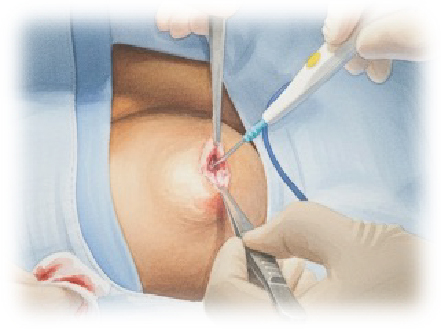

アクロサージを用いた日帰り手術(自費診療)

当クリニックでは、マイクロ波の熱を利用して組織を凝固・切開する「アクロサージ」という医療機器を導入しています。

アクロサージはマイクロ波を照射して組織を凝固させながら、剪刀(ハサミ)で切離する新しいエネルギーデバイスです。

④精巣固有鞘膜(水腫壁)の切除

アクロサージ使用により止血効果の高い切除ができる

この方法は、液体を排出した後、精巣に最も近い部分をわずかに残して、鞘膜の大部分を円形に切除します。この時、電気メスではなくマイクロ波による切開を行います。マイクロ波は組織に含まれる水分子を振動させることにより生体組織を加熱し、均一な凝固を行います。マイクロ波による凝固・止血能力と、切開することに適したハサミ型の先端を持ち合わせた世界で唯一の手術器械「アクロサージ」で手術を行います。